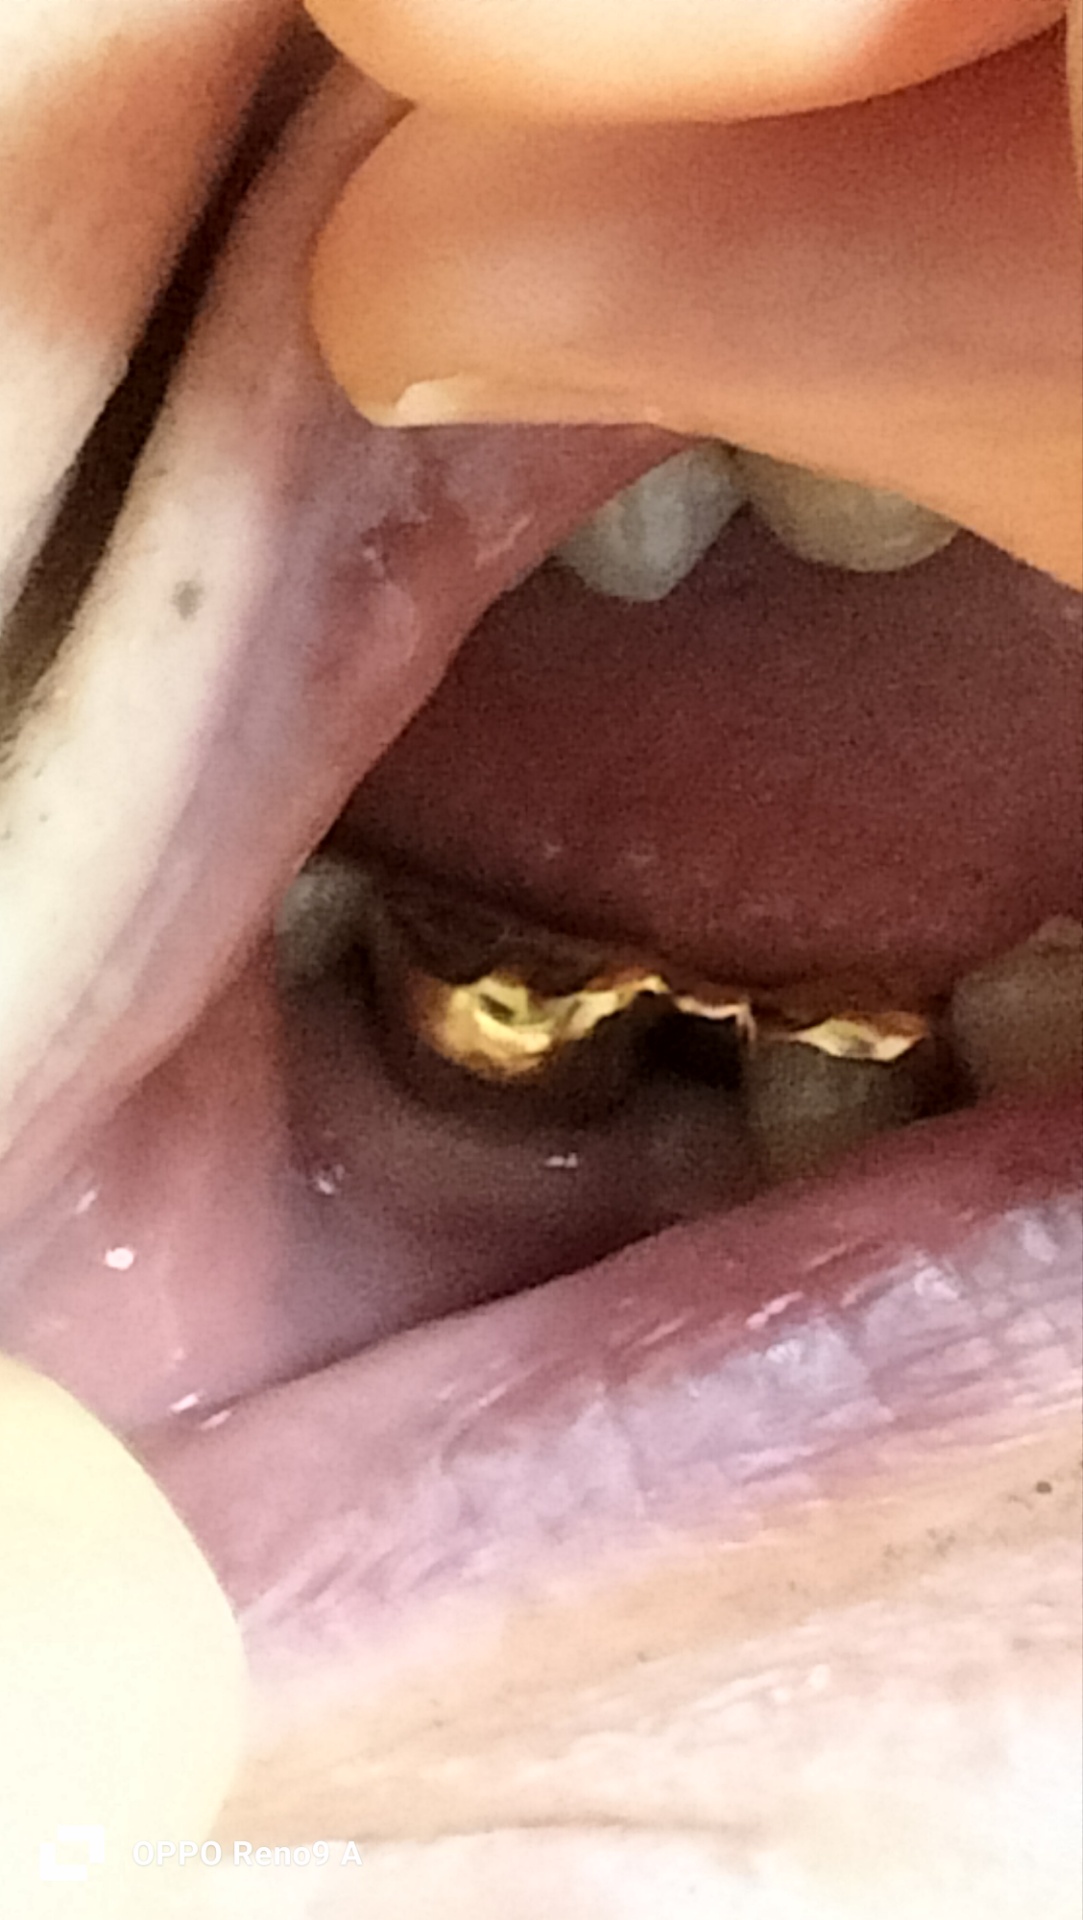

右下5番が欠損で4番と6番が金クラウンのブリッジにて形成されています(写真参照)。ブリッジは、形成してからもう40年ぐらい経っています。

画像1クラウン側面.jpg 画像2クラウン上面.jpg

写真を見ると5番の隙間がそれほどないように見えるので、4番6番の単冠、連結冠も考えられるかなと思いました。